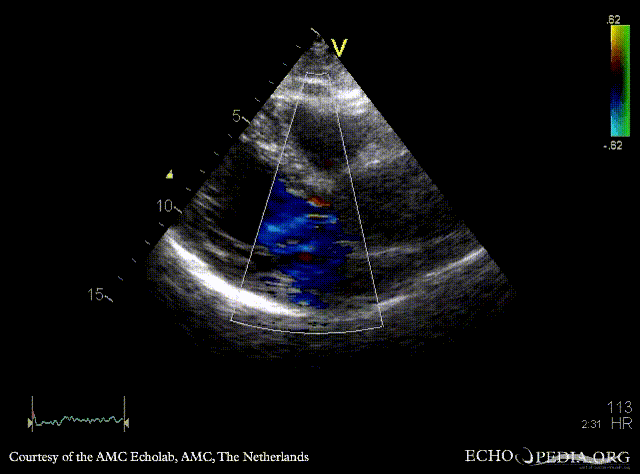

30 Aortic dissection

PLAX: dilated aortic root and ascending aorta PLAX: Color Doppler, mild aortic regurgitation